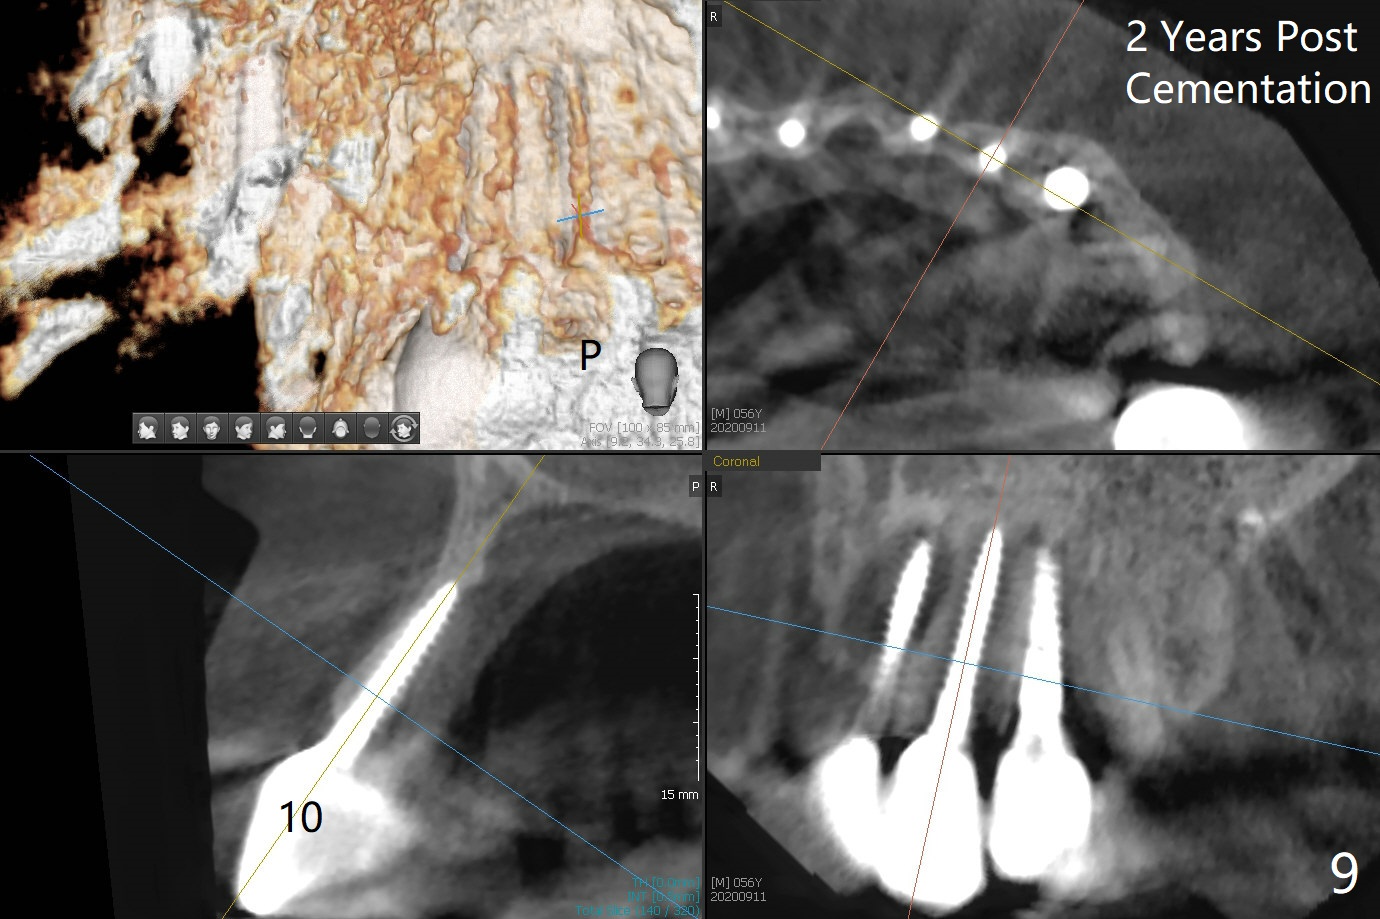

There is no obvious black triangle between the implants at #8-11 (Fig.1 post infiltration). Following papilla (Fig.2 *) sparing incision and elevation of the buccal flap, the fenetration of the buccal plate around the socket shield (Fig.3 S) is found at #11; there is a distal defect with granulation tissue (*). After shield and granulation tissue removal, the coronal implant is found exposed (Fig.4 until osteotomy). The relatively flat surface of IBS implant is apparently less likely to develop periimplantitis. With periosteal relief and placement of sticky bone (Fig.7 *), PRF and 6-month membrane, the wound is closed with 4-0 PTFE suture (Fig.5). Failure of socket shield is related to retention of the apex (Fig.6 <). Probe before extraction and remove apex and gutta percha. There appears no buccal or palatal (P) defect 9 months post shield removal (17 months post cementation, Fig.8), although the bone density palatally is low. Although the sagittal section (Fig.9 (lower left panel) shows the absent palatal plate at #10, the 3-D image and the coronal section do not (upper let and right panels). The 2.5 mm implant at #9 appears to have been placed buccal (Fig.10 B), although the buccal crest is present. In contrast the 2.5 mm implant at #8 appears within the bone boundary (Fig.11). The soft tissue remains healthy at #8-11. Bone graft will be done if needed.